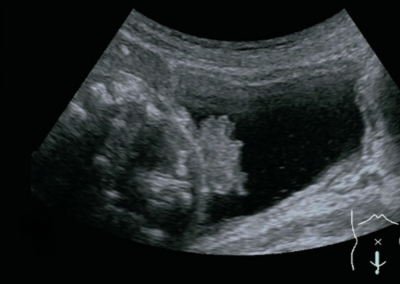

尿所見:蛋白(−)、糖(−)、ケトン体(−)、潜血 3+、沈渣に赤血球 100以上/HPF、白血球1~4/HPFを認める。腹部超音波検査と膀胱鏡所見とを別に示す。